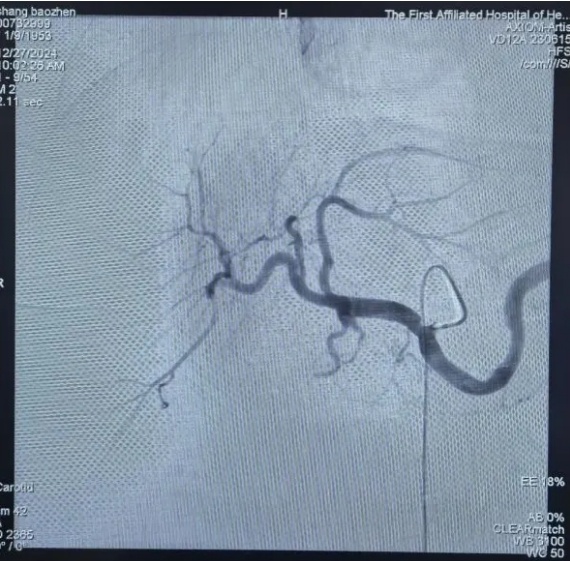

该医院在治疗患者肝脏多发病变过程中,采纳了DSA技术辅助的精确手术方法。手术于20XX年X月X日实施,患者接受了局部麻醉,并通过股动脉穿刺成功置入导管。导管尖端精准定位至肝总动脉。随后,运用高压注射器进行造影,清晰显现了肝左叶病灶的供血动脉路径。继而,将微导管送入肝左动脉,并注入了含碘化油的乳化剂。

手术过程中观察到,碘化油在肝脏左侧病变区域显著聚集,显示出药物在此区域的滞留效果显著。为此,术中采取了分次缓慢注射的方法,以提升疗效并降低潜在副作用。此技术能精确阻断肿瘤血供,最终实现病灶消融。